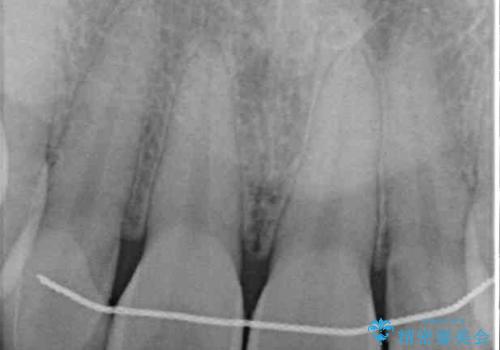

- 前歯のラミネートベニアの不自然な色合いを気にして来院された患者様です。

矯正治療後戻り防止のワイヤー周りにむし歯があったため、オールセラミッククラウンにて補綴することとしました。